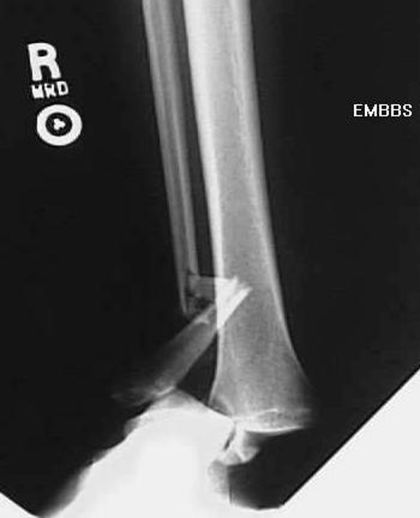

盖氏骨折

桡骨骨折

远侧尺桡关节分离